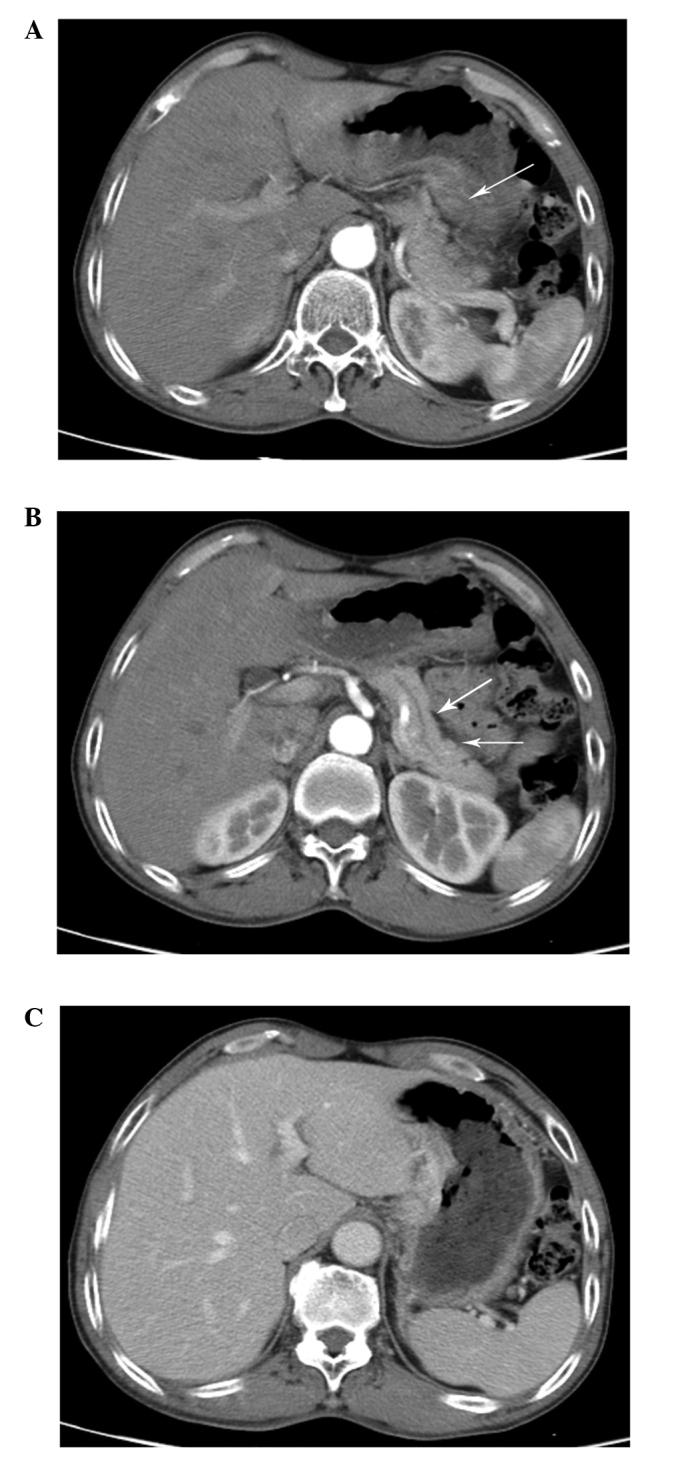

A 60-year-old male was referred to Nanjing Drum-Tower Hospital (Nanjing, Jiangsu, China) due to the presence of gastric carcinoma. A biopsy was performed under an electronic gastroscope and the pathological analysis resulted in the diagnosis of gastric small cell carcinoma (GSCC). The mass had invaded the liver and the pancreas according to an enhanced computed tomography scan, thus current surgical methods were considered to be of high risk and highly challenging. Following four cycles of neoadjuvant chemotherapy with irinotecan (200 mg, days 1, 21, 41 and 61) and oxaliplatin (120 mg, days, 1, 21, 41 and 61) the patient underwent a D2 gastrectomy and an esophagojejunal Roux-en-Y anastomosis, followed by adjuvant chemotherapy. The patient experienced survival without progression in the 8-month follow-up. To the best of our knowledge, this is one of few cases of GSCC treated with the combination of neoadjuvant chemotherapy, surgery and adjuvant chemotherapy.

一名60岁男性因患胃癌被转诊至南京鼓楼医院(中国江苏南京)。在电子胃镜下进行了活检,病理分析确诊为胃小细胞癌(GSCC)。根据增强计算机断层扫描,肿块已侵犯肝脏和胰腺,因此目前的手术方法被认为风险高且极具挑战性。在接受了四个周期的新辅助化疗,使用伊立替康(200mg,第1、21、41和61天)和奥沙利铂(120mg,第1、21、41和61天)后,患者接受了D2胃切除术和食管空肠Roux-en-Y吻合术,随后进行辅助化疗。在8个月的随访中,患者存活且无疾病进展。据我们所知,这是少数几例采用新辅助化疗、手术和辅助化疗联合治疗GSCC的病例之一。